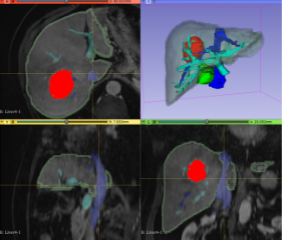

Making the models is a multi-step process; it begins when a doctor orders a medical imaging scan. The patient visits the radiology department for their scan, and X-ray technicians take a lot of images in sequence, moving across a section of the patient's body. For certain procedures, such as surgery to remove cancer, the Health Design Lab team can take those same imaging slices and create a digital 3D rendering. This is done by coloring in the desired areas on each 2D image, slice by slice, and using special software to turn this into a new three-dimensional file (a 3D rendering). This rendering is an exact 3D replica of the anatomy that is important in each patient’s case.

This digital rendering is then prepared into a format that a 3D printer can read, keeping into consideration things like the color of the material and the size of the model. Using the 3D information we send it, the printer builds up the model layer by layer. Now, a real organ--first fully digitized--exists as an almost exact plastic replica back in the real world. When printing different organs, various colored plastics can be used together to make a more complex model. If surgery is needed to remove a tumor, it can be printed using a different color than the organ it is growing in, so it is easier to see on the final model.

An example is currently on display in The Franklin Institute's Tech Studio: a model of hepatocellular carcinoma, a common liver tumor that a patient needed to have surgically removed. During the surgery, a section of the liver surrounding it also needs to be removed, along with other nearby organs blocking the surgeons' way. It is hard to appreciate this on a CT or MRI scan because the tumor in the liver is about three computer mouse scrolls away from a nearby organ, the gallbladder, that sits in front of it, so they don't appear on the 2D image. This causes confusion, as patients don't often understand why removing the gallbladder is necessary if the tumor is in the liver. However, when holding the 3D model in their hands, they see clearly that the neighboring organ also needs to come out to remove the tumor.